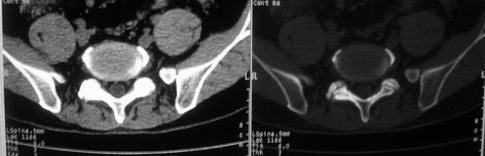

以下是引用余辉在2008-10-23 16:14:00的发言:[br]腰椎体棱角分明,小关节退变部分隔合,骶髂关节部分融合,考强脊炎